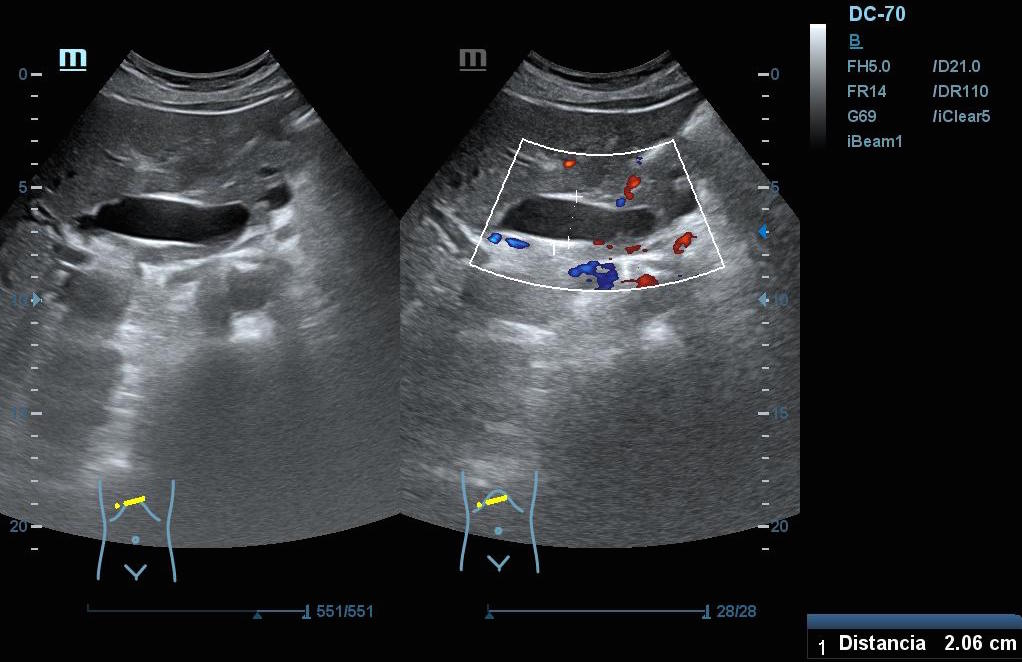

Hallazgos ecográficos: En el epigastrio se observa una imagen anecoica tubular, sin captación en Doppler, con un diámetro mayor a 2 cm, que sugiere una dilatación del colédoco (imagen 1). La vesícula biliar se encuentra completamente distendida y hepatizada, con una imagen en «doble cañón de escopeta» sugestiva de colestasis (imagen 2). En los cortes longitudinales se identifica una masa anterior a la aorta en el corte paramedial izquierdo, aparentemente localizada en el cuerpo del páncreas (imagen 3). En los cortes transversales se observa una masa que afecta tanto al cuerpo como a la cabeza del páncreas (imagen 4).